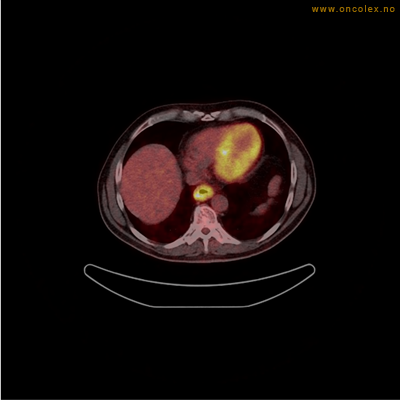

Eksempler på funn

Vev som tar opp mer radioaktivt stoff, synes som hvite områder som lyser opp mer i forhold til annet vev som tar opp mindre sukker.

Spredningssvulster til lever med sentral nekrose.